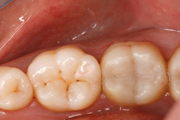

Mit aktuellen Kunststoffmaterialen lassen sich ästhetische und langlebige Füllungen realisieren. Sie sind in verschiedenen Weißtönen erhältlich und können so individuell dem Zahn angepasst werden, wie an den Fotos oben zu sehen: hier wurde eine Amalgamfüllung durch eine Kunststoff-Füllung ersetzt. Ein weiterer Vorteil besteht in der zahnsubstanzschonenden Behandlung. Es muss nur wirklich kariöses Material vom Zahn abgeschliffen werden. Die korrekte Verarbeitung dieser Materialien ist sehr aufwendig, verbunden mit hohen Materialkosten. Die gesetzlichen Krankenkassen übernehmen die Kosten für Kunststoff-Füllungen im Backenzahnbereich nur bei nachgewiesener Allergie gegen Amalgam (Allergiepass). Je nach Größe der Kunststofffüllung fällt deshalb eine Zuzahlung für Sie an.